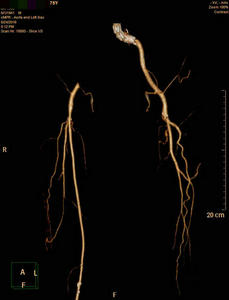

术前CTA提示腹主动脉支架右髂支闭塞